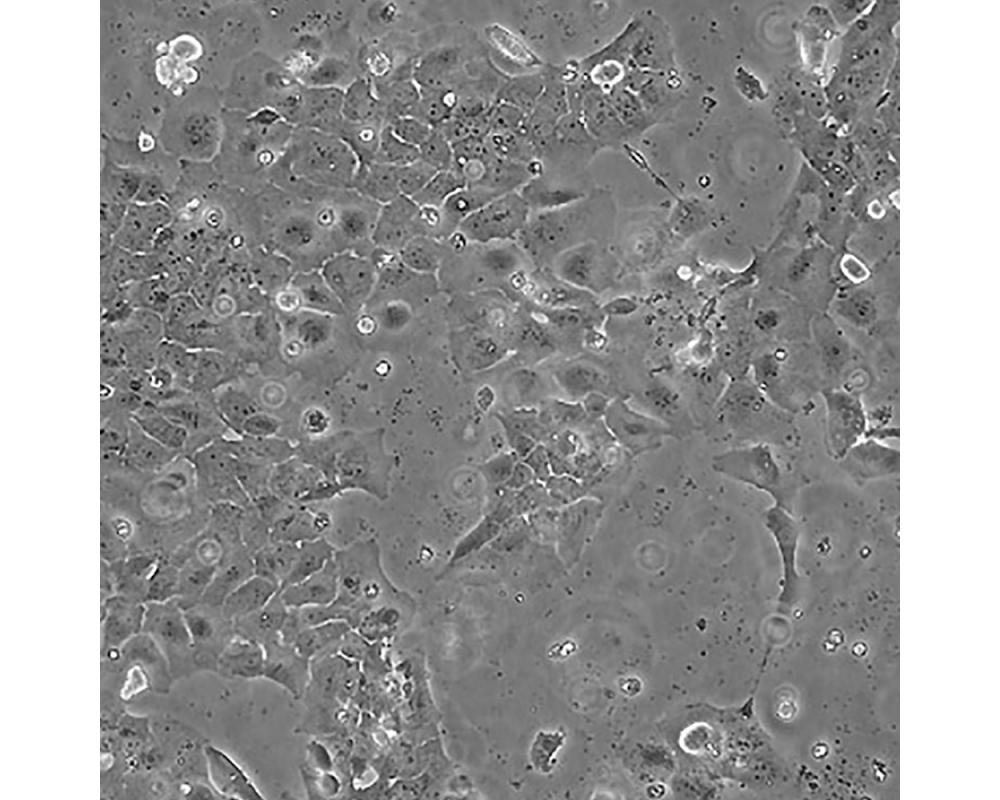

CAOV-3

中文名稱 人卵巢癌細胞

組織來源 卵巢癌;女性

形態(tài)特征 上皮樣

生長特性 貼壁生長

特征特性 該細胞1976年建系,源自一位54歲白人女性的卵巢腺癌組織。